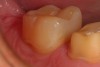

Figure 9. A two-week post operative view of the mesial occlusal bulk filled composite restoration in tooth number 31 prior to placement of the ceramic restoration on tooth number 30. Note the seamless margin between the restorative material and the tooth with no manipulation or “condensing” of the composite material during placement.

Figure 9